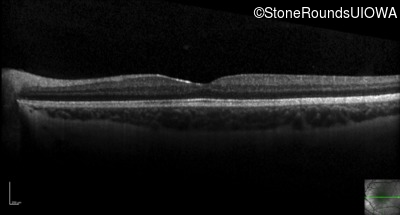

Optical Coherence Tomography - Right - 20/50 -1

Exemplar / OCT Stack